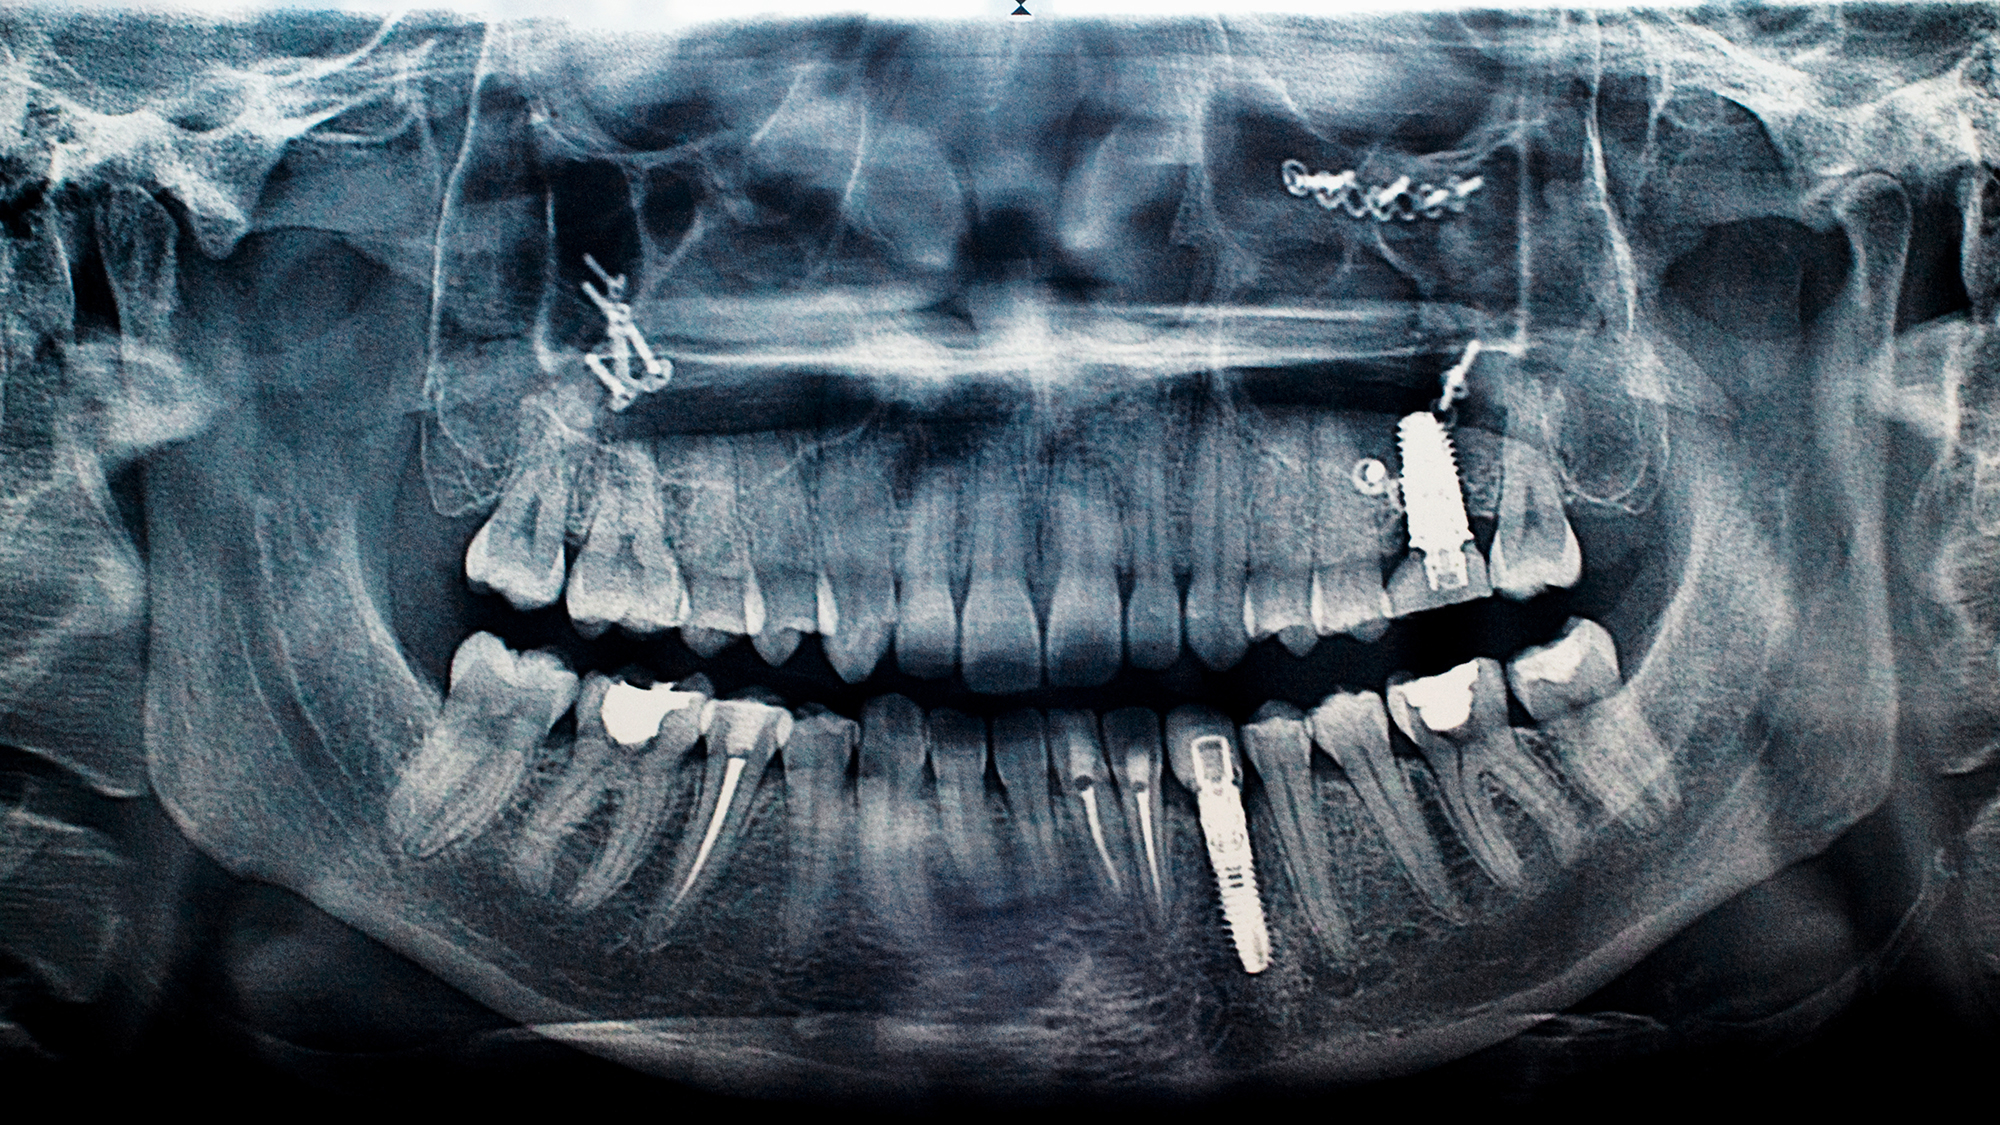

Dental implants have been used to replace damaged or missing teeth for decades. They generally consist of a metal anchor screwed into the bone, then capped with a prosthetic tooth, commonly made of porcelain.

Dental implants have been used to replace damaged or missing teeth for decades. They generally consist of a metal anchor screwed into the bone, then capped with a prosthetic tooth, commonly made of porcelain. Credit: E+/Getty Images

In its simplest form, implant surgery involves extracting a single tooth and replacing it with a metal post that is screwed into the jaw and then affixed with a prosthetic tooth commonly made of porcelain, also known as a crown. Patients can also use “full-arch” or “All-on-4” implants to replace all their upper or lower teeth — or all their teeth.